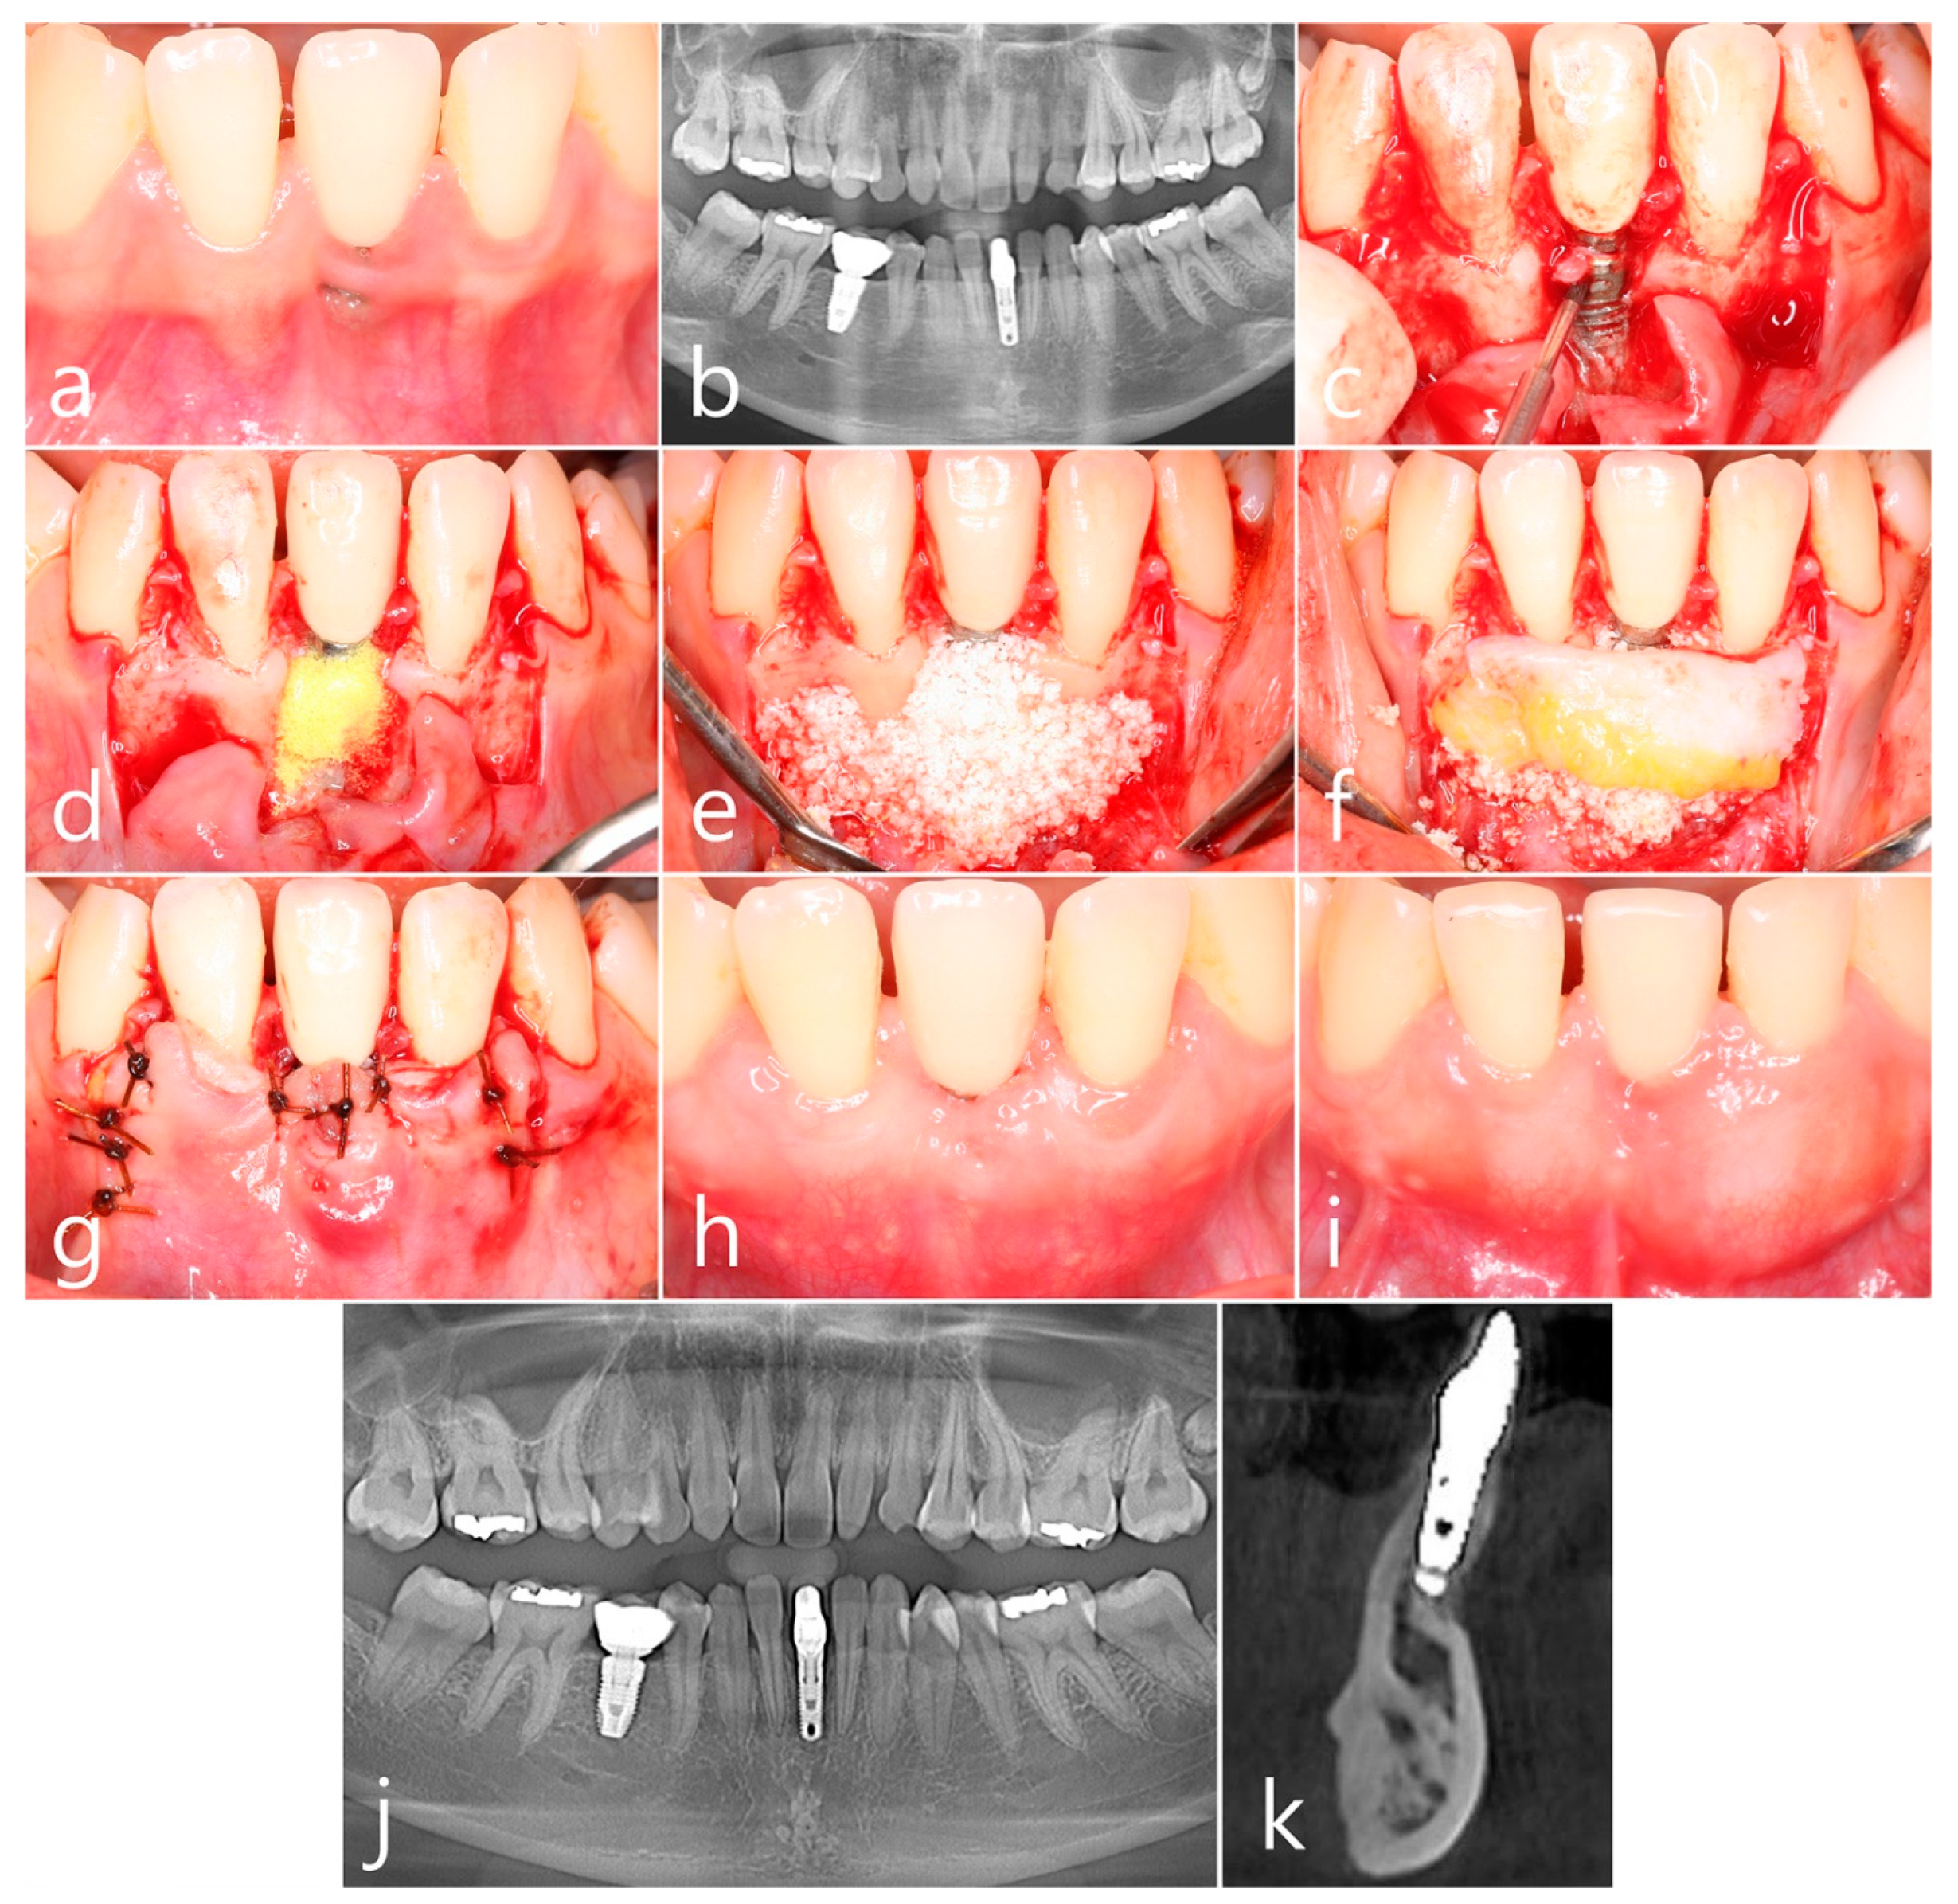

2.4. Case 4